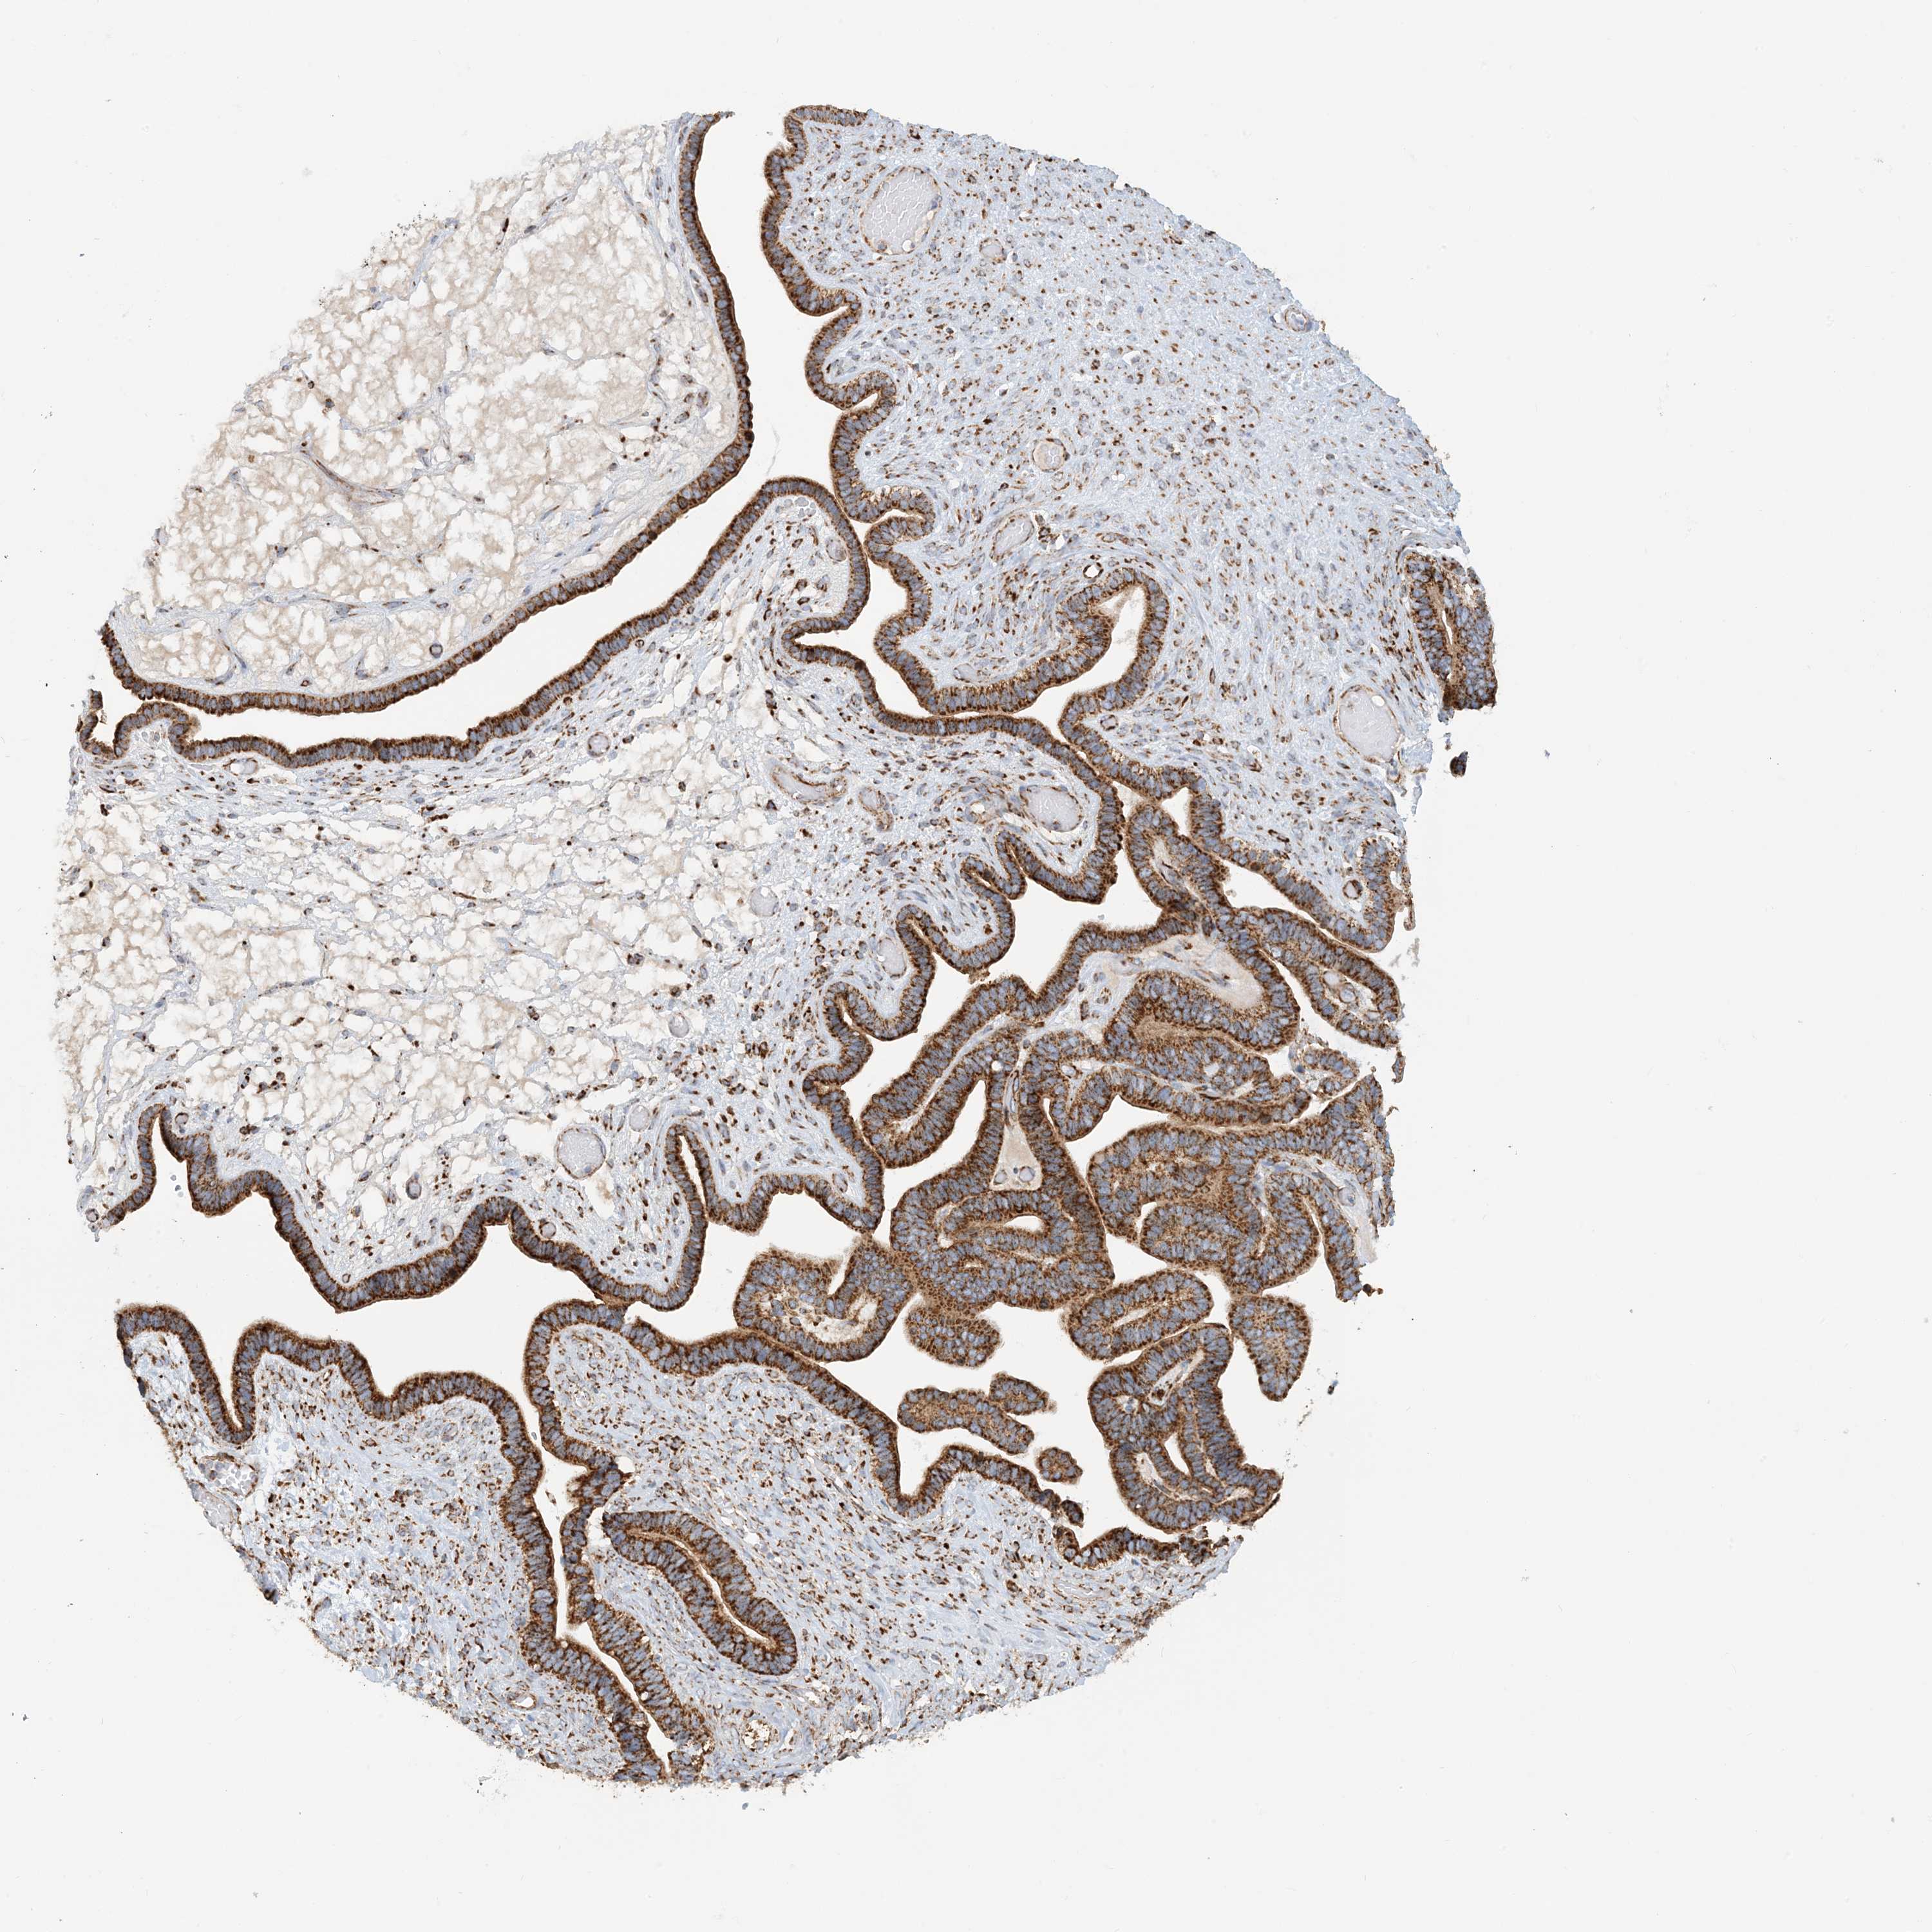

OVARIAN CANCER - Protein expressioni

A mouse-over function shows sample information and annotation data. Click on an image to view it in a full screen mode. Samples can be filtered based on level of antibody staining by selecting one or several of the following categories: high, medium, low and not detected. The assay and annotation is described here.

Note that samples used for immunohistochemistry by the Human Protein Atlas do not correspond to samples in the TCGA dataset.

Antibody stainingi

Antibody staining in the annotated cell types in the current human tissue is reported as not detected, low, medium, or high, based on conventional immunohistochemistry profiling in selected tissues. This score is based on the combination of the staining intensity and fraction of stained cells.

Each image is clickable and will lead to virtual microscopy that enables deeper exploration of all samples and also displays staining intensity scores, fraction scores and subcellular localization as well as patient and tissue information for each sample.

Antibody HPA031966

Staining

High

Medium

Low

Not detected

Intensity

Strong

Moderate

Weak

Negative

Quantity

>75%

75%-25%

<25%

None

Location

Nuclear

Cytoplasmic/membranous

Cytoplasmic/membranous,nuclear

Cystadenocarcinoma, serous, NOS

Carcinoma, endometroid

Cystadenocarcinoma, mucinous, NOS

Carcinoma, NOS